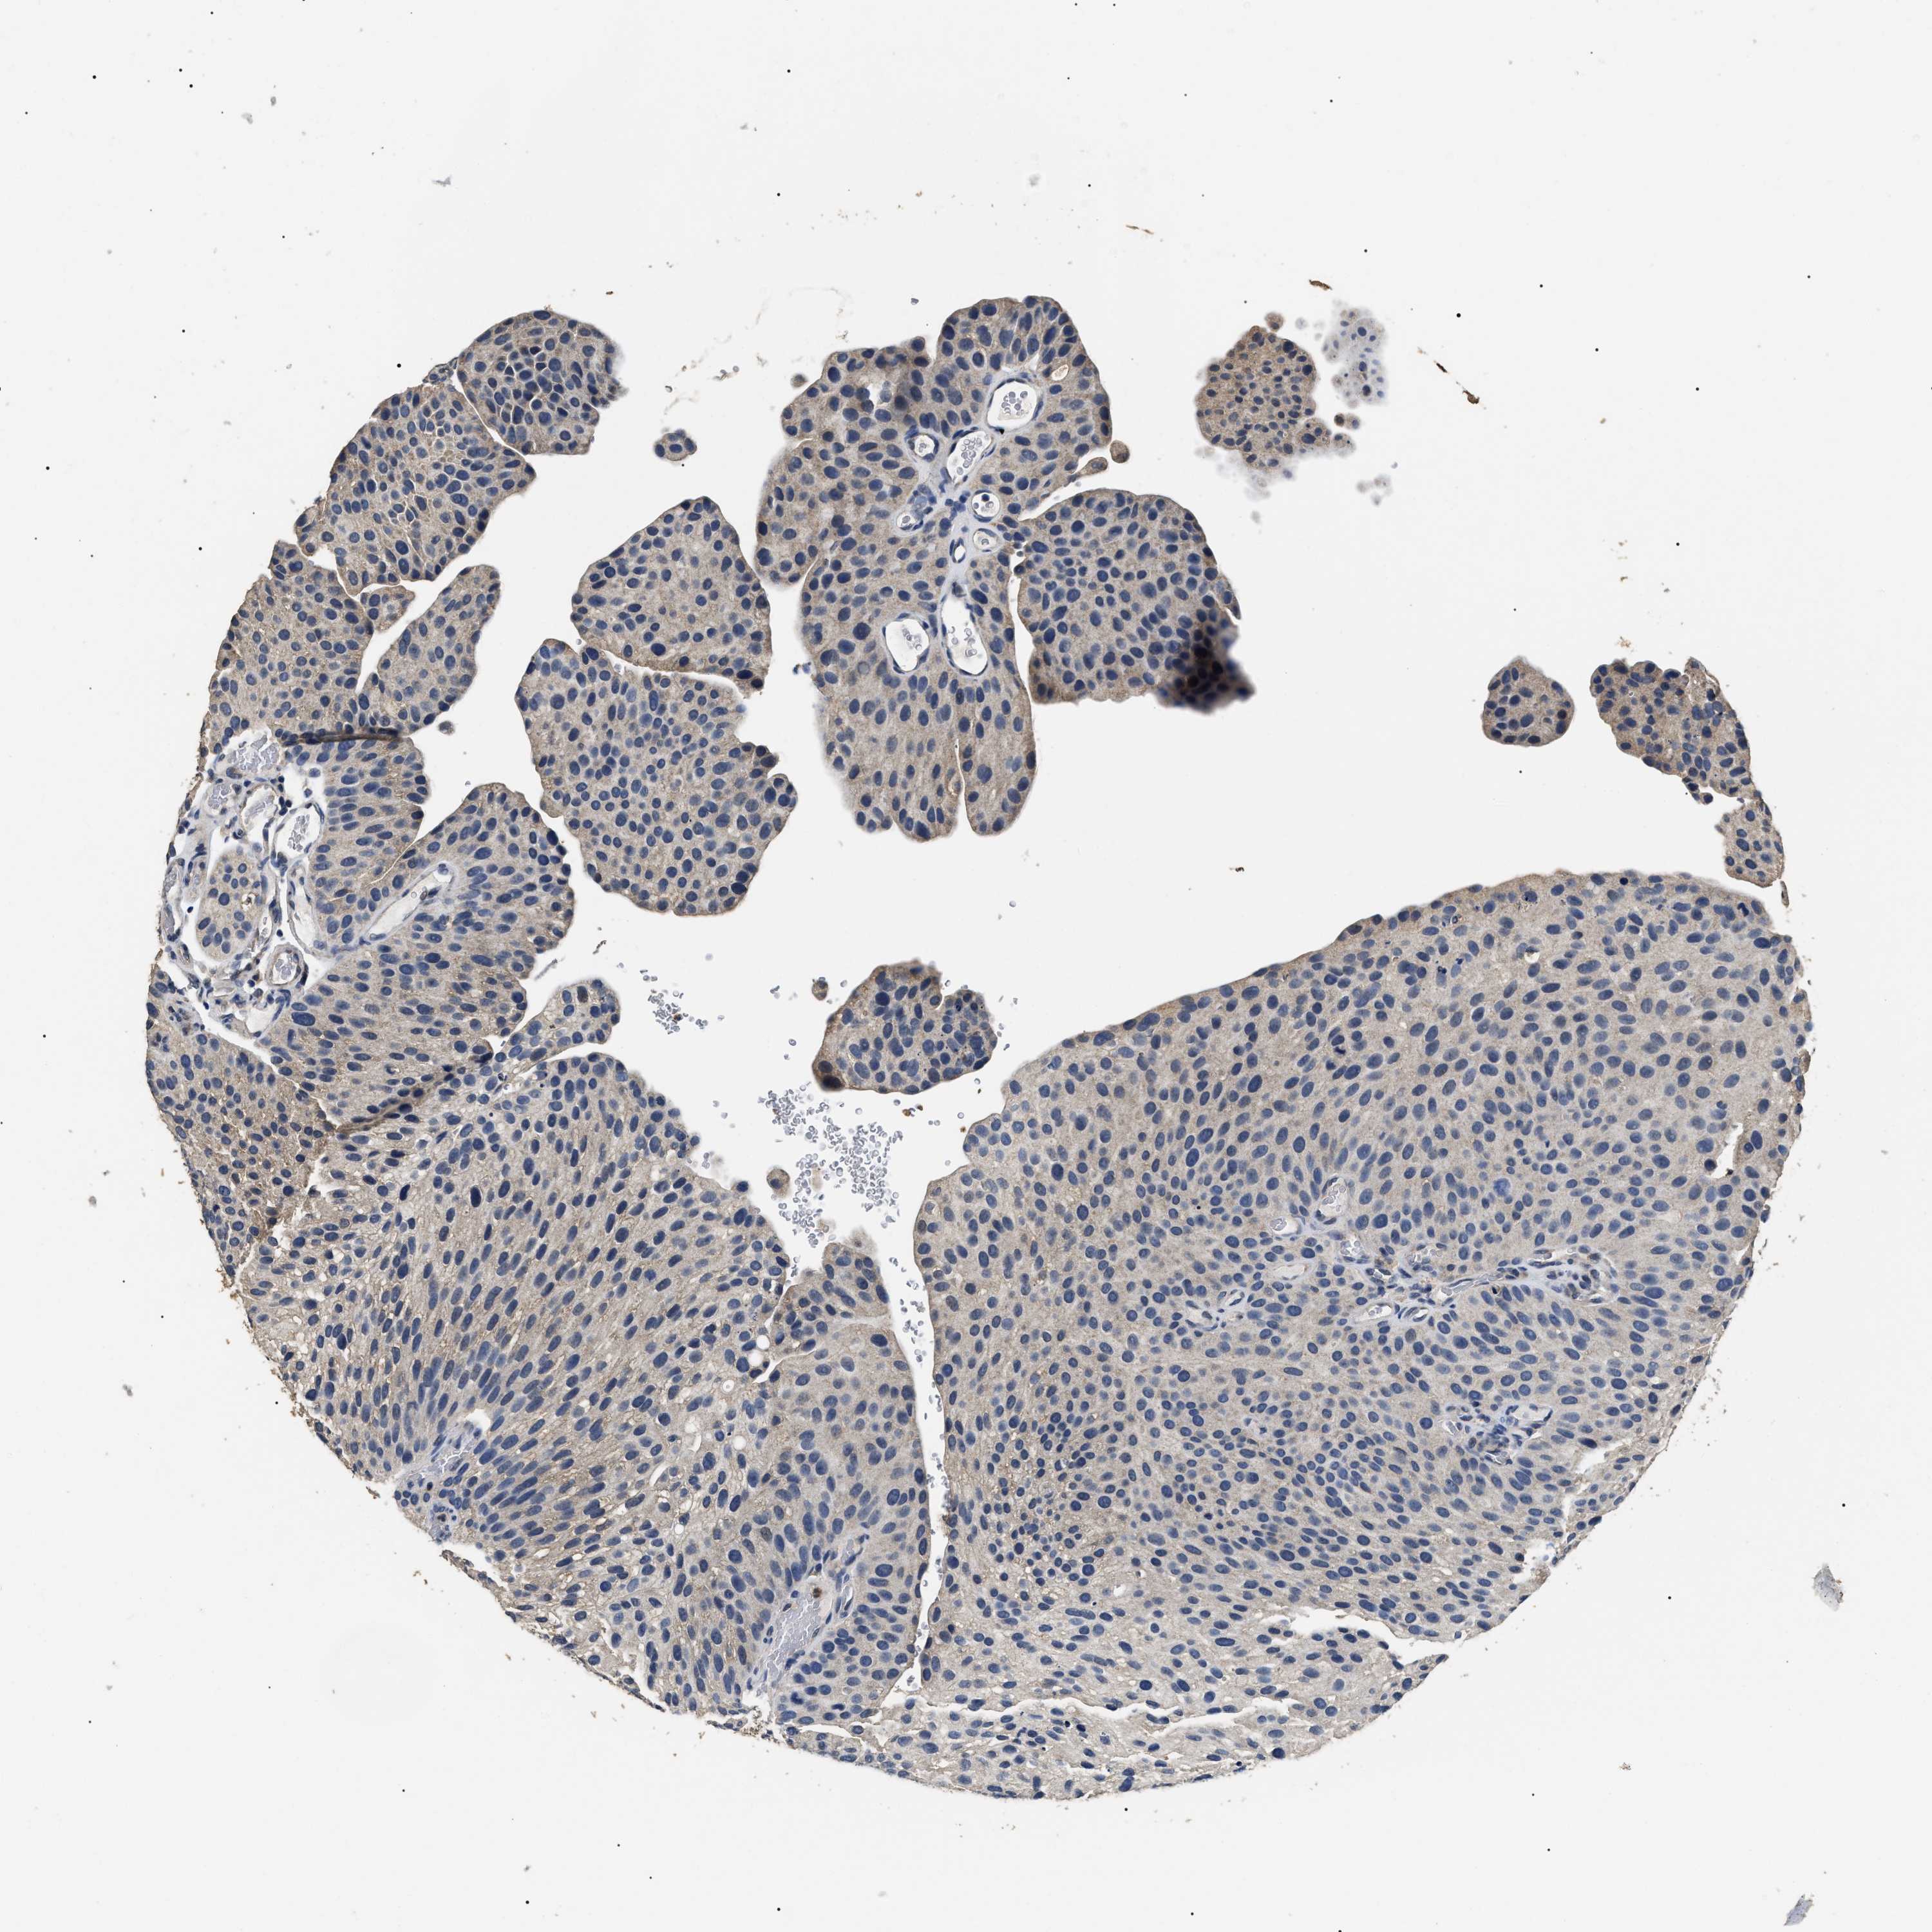

UROTHELIAL CANCER - Protein expressioni

A mouse-over function shows sample information and annotation data. Click on an image to view it in a full screen mode. Samples can be filtered based on level of antibody staining by selecting one or several of the following categories: high, medium, low and not detected. The assay and annotation is described here.

Note that samples used for immunohistochemistry by the Human Protein Atlas do not correspond to samples in the TCGA dataset.

Antibody stainingi

Antibody staining in the annotated cell types in the current human tissue is reported as not detected, low, medium, or high, based on conventional immunohistochemistry profiling in selected tissues. This score is based on the combination of the staining intensity and fraction of stained cells.

Each image is clickable and will lead to virtual microscopy that enables deeper exploration of all samples and also displays staining intensity scores, fraction scores and subcellular localization as well as patient and tissue information for each sample.

Antibody HPA006702

Antibody CAB021101

Staining

High

Medium

Low

Not detected

Intensity

Strong

Moderate

Weak

Negative

Quantity

>75%

75%-25%

<25%

None

Location

Nuclear

Cytoplasmic/membranous

Cytoplasmic/membranous,nuclear

Urothelial carcinoma, Low grade